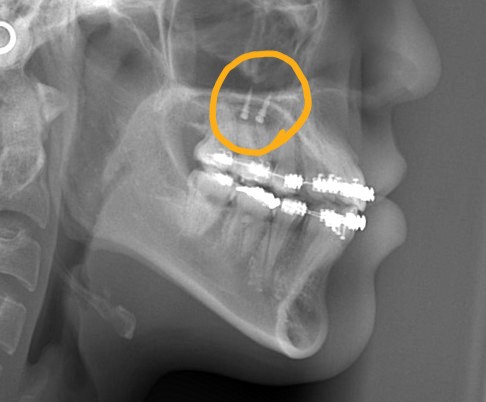

そこで、真ん中を合わせるために、口蓋にアンカースクリューを植立して「力」を加えることにしました。

約2か月、期間を空けてアンカースクリューが落ち着いたところで、PLASという付属品を付けて、上下の正中を合わせるように試みます。

レントゲン写真でも比較してみましょう

左側が矯正治療前、右側が矯正治療後